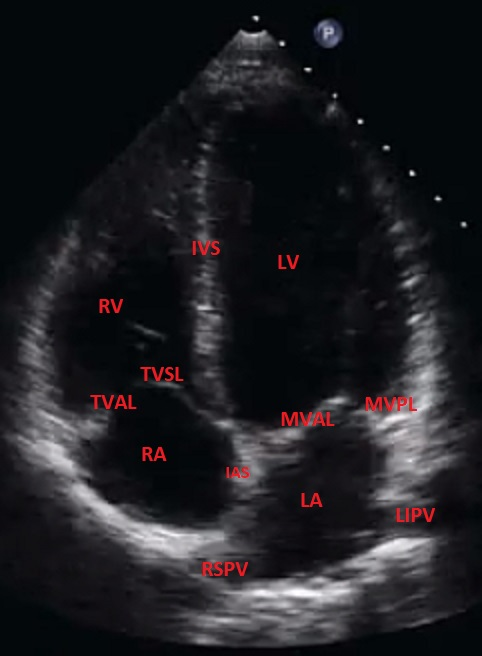

Draw and label the apical 4 chamber view.

Optimal for assessing integrity of the IAS and IVS because the sound beam is perpendicular.

What structures tend to drop out in apical 4-chamber and why?

IAS and IVS - these structures are parallel to the sound beam in apical window.